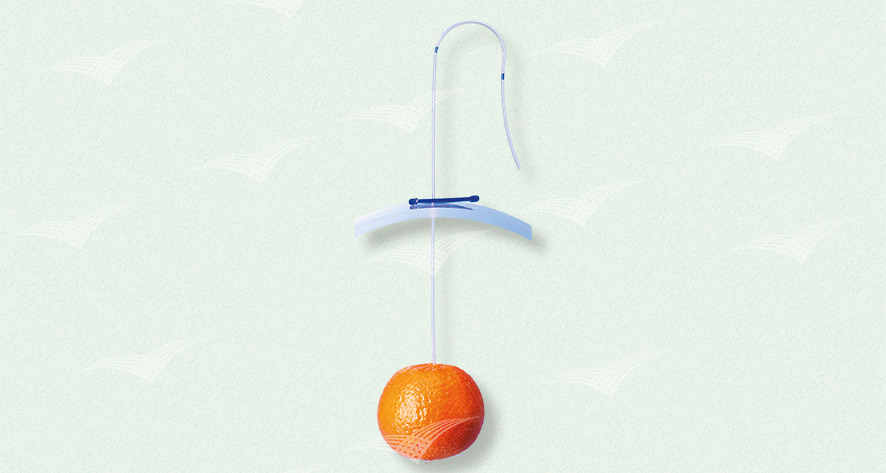

Laparoskopisches Gewebe Retraktionssystem T’Lift

Steriles Set enthält: 2x T’Lift, 1x Einführkanüle, 2x Schiebklemme

T’Lift fixiert selbständig bis zu 1 kg und benötigt keinen eigenen Trokarzugang